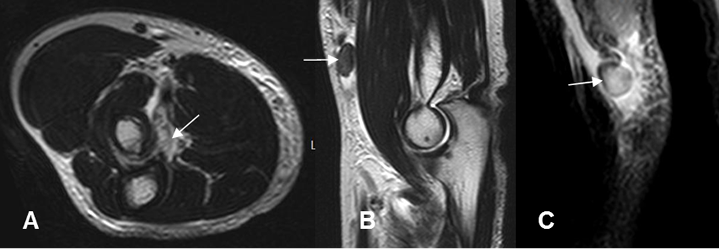

Fig 40 B. Ruptura del bíceps.

A: RM axial en T2: Ausencia del tendón del bíceps a nivel de su inserción, por ruptura.

B: RM sagital en T2 y C: RM sagital en STIR. Ruptura retraida del bíceps, con fragmento óseo asociado, por avulsión.